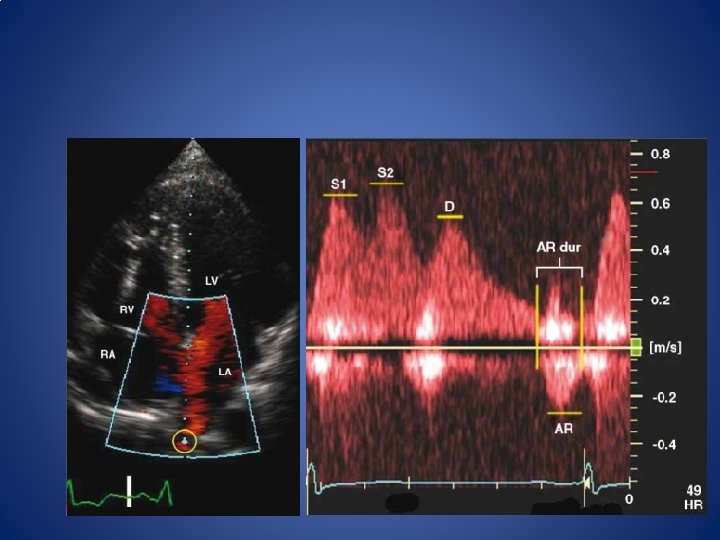

Pulmonary venous flow - acquisition • Apical 4 chamber • PW • Sample volume 2 mm-3 mm > 0. 5 cm into the pulmonary vein • Wall filter settings must be low enough to display the onset and cessation of the atrial reversal (Ar) velocity waveform • sweep speed of 50 to 100 mm/s at end expiration; average of >/=3 consecutive cardiac cycles.

PULMONARY VENOUS WAVE FORM • peak systolic (S) velocity, peak anterograde diastolic (D) velocity , the S/D ratio systolic filling fraction (Stime-velocity integral/[Stimevelocity integral? • D time-velocity integral]) and the peak Ar velocity in late diastole. • Other measurements are the duration of the Ar velocity, the time difference between it and mitral Awave duration (Ar ? A) • and D velocity DT. • There are two systolic velocities (S 1 and S 2